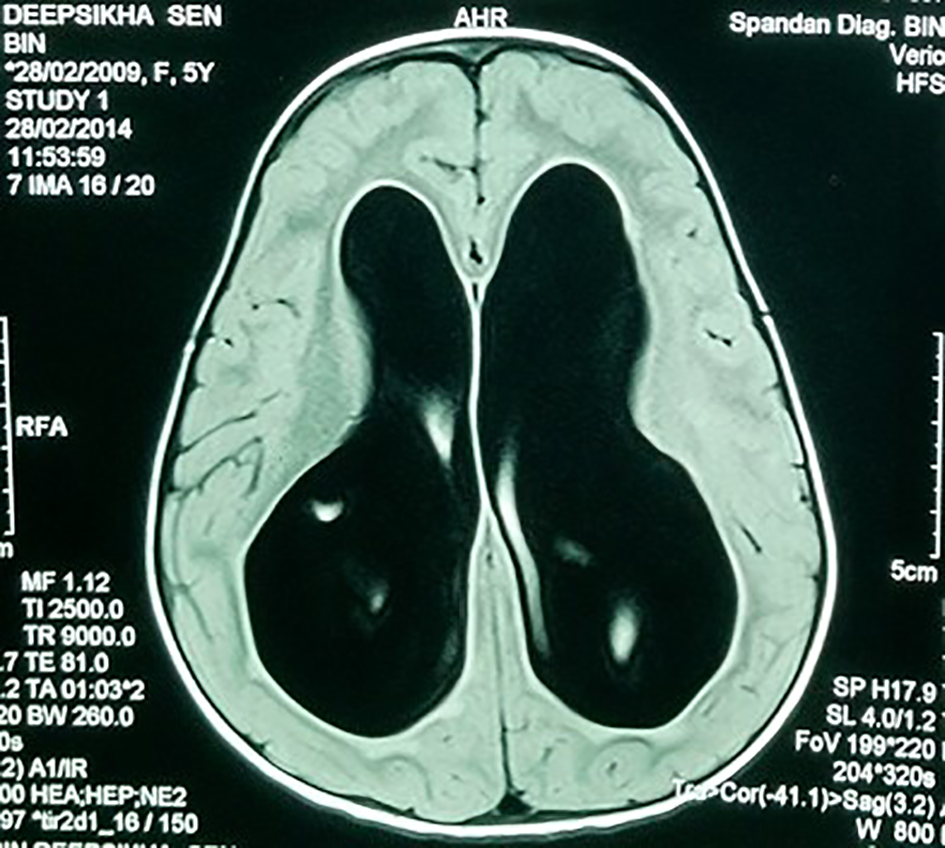

A 7-year-old girl presented with progressive head enlargement since birth, features of raised intracranial pressure in the form of headache, vomiting, excessive crying and excessive drowsiness. Her visual acuity was reduced due to secondary optic atrophy. She had no history of any seizures since birth. Magnetic resonance imaging (MRI) revealed a large hypointense lobulated mass (T2 and FLAIR) originating from the choroid plexus in the temporal horn of the right lateral ventricle measuring almost 50 × 45 × 40 mm in size. All supratentorial ventricles were dilated and the mass was causing compression over adjoining midbrain (Figs. 1-3). With a provisional diagnosis of a choroid plexus mass, the patient was taken up for surgery. A ventriculo-peritoneal shunt was placed for the drainage of excessively forming CSF 2 days prior to the surgery. A right temporal craniotomy was performed and the temporal horn was opened through mid temporal sulcus and the mass was reached. It was a firm friable and vascular mass arising from the choroid plexus on the temporal horn. The tumor had its vascular supply from the anterior choroidal artery.

![]() Click for large image | Figure 1. MRI showing large bilateral hydrocephalus. |